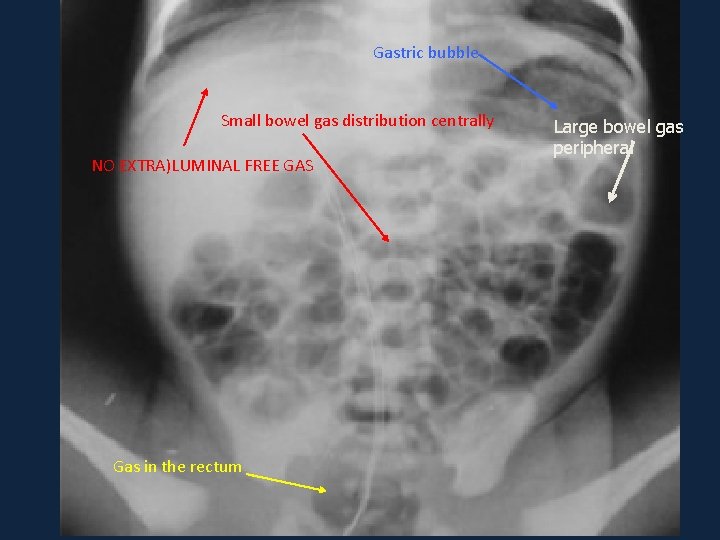

Systematic approach ►Air: ►B ►C ►D ►E • Extra-luminal air – always pathological. • Intra-luminal air – it depends on the distribution

Gastric bubble Small bowel gas distribution centrally NO EXTRA)LUMINAL FREE GAS Gas in the rectum Large bowel gas peripheral